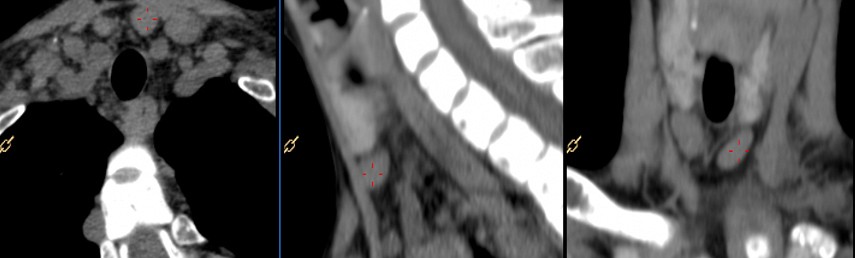

Nos envían a este paciente para realizarle un gammagrama paratiroideo y un estudio SPECT/CT con 99mTc-MIBI ante la sospecha clínica de un adenoma paratiroideo. La gammagrafía paratiroidea es un estudio de Medicina Nuclear que se utiliza para localizar tejido paratiroideo hiperfuncionante, particularmente en pacientes con datos clínicos y bioquímicos compatibles con hiperparatiroidismo. Contexto clínico y objetivo del estudio.En pacientes con sospecha de hiperparatiroidismo, la localización precisa de las glándulas paratiroides hiperfuncionantes es fundamental para una adecuada planeación terapéutica. La gammagrafía paratiroidea permite evaluar el comportamiento funcional del tejido paratiroideo, aportando información que no siempre es visible en estudios de imagen anatómica. Metodología del estudio y hallazgos en la gammagrafía.

Aportación del SPECT/CT al diagnóstico.

El SPECT/CT permite correlacionar áreas de captación aumentada del radiofármaco con estructuras anatómicas específicas, facilitando una localización precisa de adenomas paratiroideos.